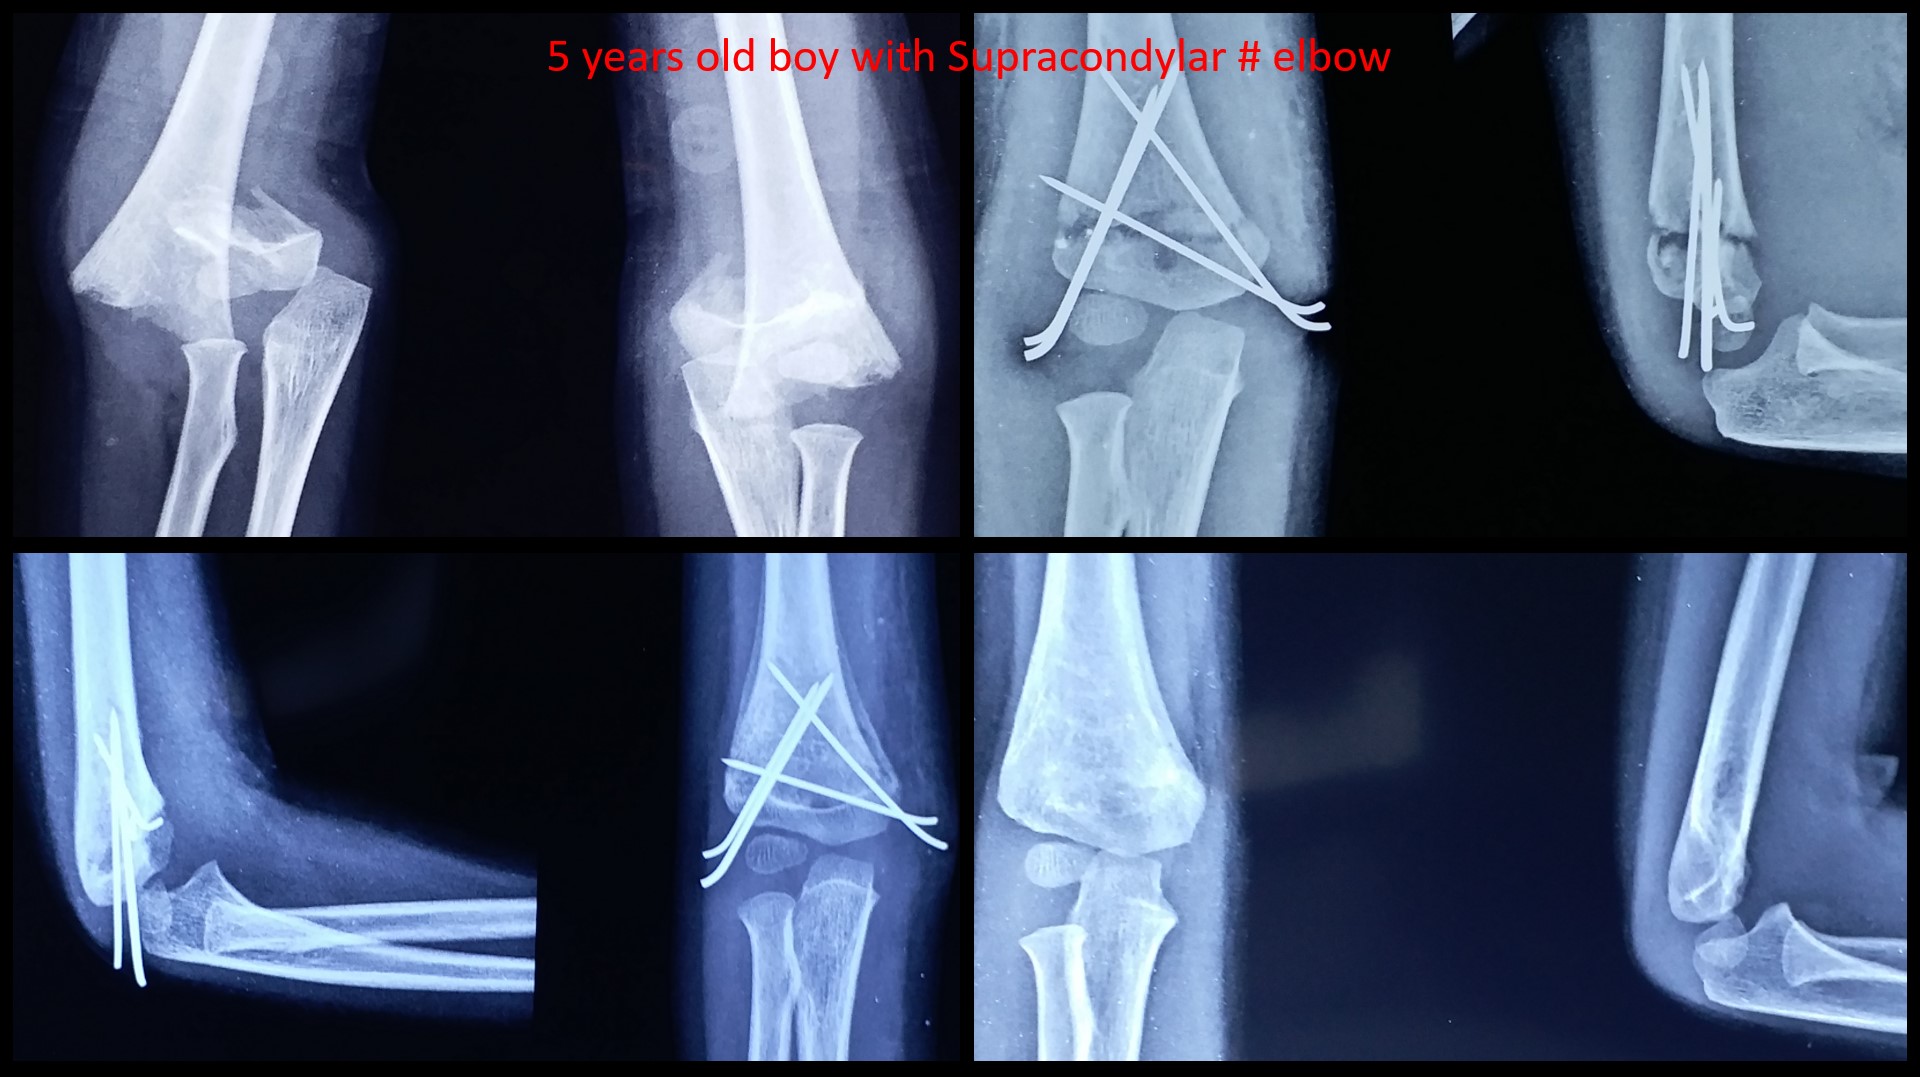

SUPRACONDYLAR #